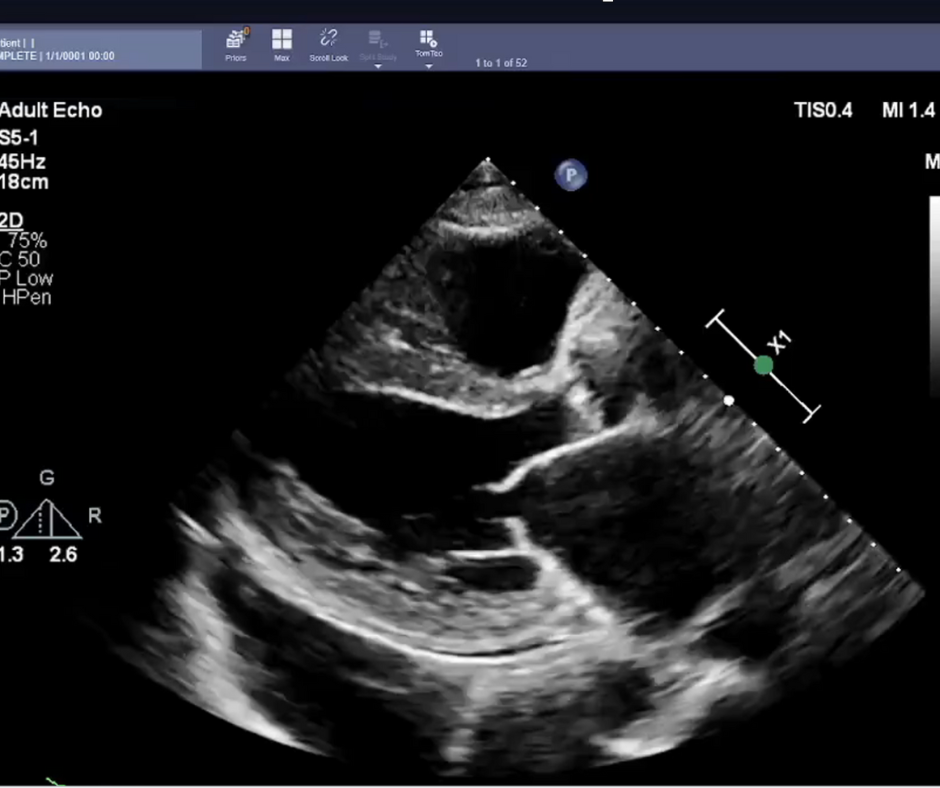

In comparison to initial sonographer assessment of echocardiograms, cardiologists are over 10 percent less likely to change initial artificial intelligence (AI) assessment of left ventricular ejection fraction (LVEF), according to new research recently presented at the European Society of Cardiology Congress in Barcelona, Spain.